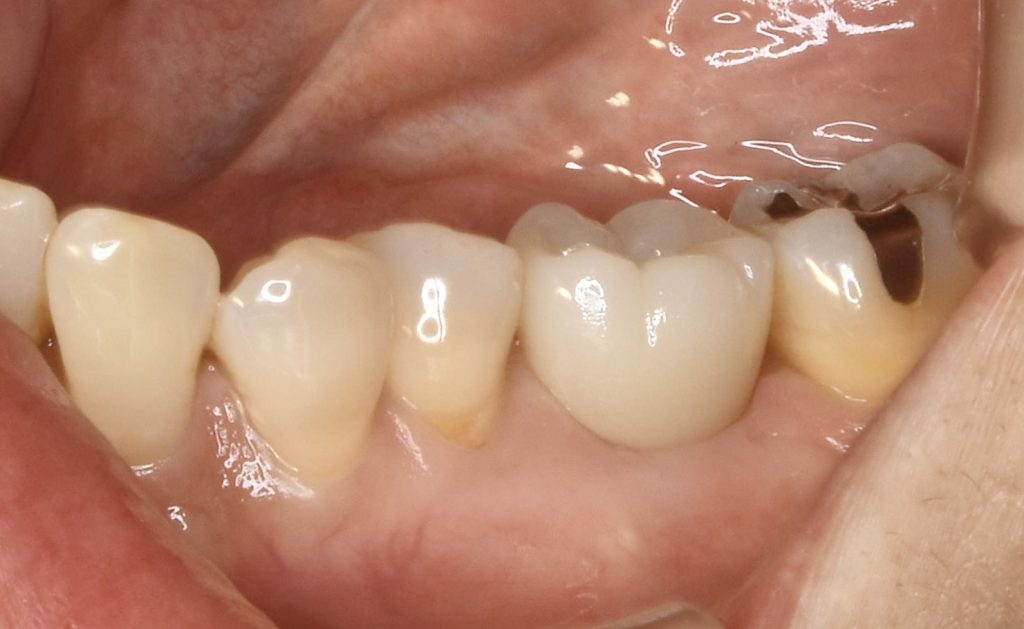

3ヶ月後、固定式のセラミッククラウンを装着し治療を終了する事が出来ました。

治療費用   約65万円(税抜)